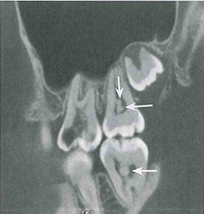

【影像学表现】牙髓钙化X线表现有两种类型,一是局限性,表现为髓石;一是弥散性,表现为髓室及根管钙化。局限性髓石与髓室形状有一定关系。后牙髓石往往表现圆形或卵圆形,大小不一。髓石可游离于髓室内,也可附着于髓室壁。前牙髓室较小,髓石可呈条状或针状充满于髓室及根管内,其周围有线状低密度影像围绕。弥散性牙髓钙化表现为正常髓室及根管影像完全消失,不能辨别出髓腔界限。有的髓腔尚可见,但变得很细,这种情况通常影响牙髓和根管治疗。